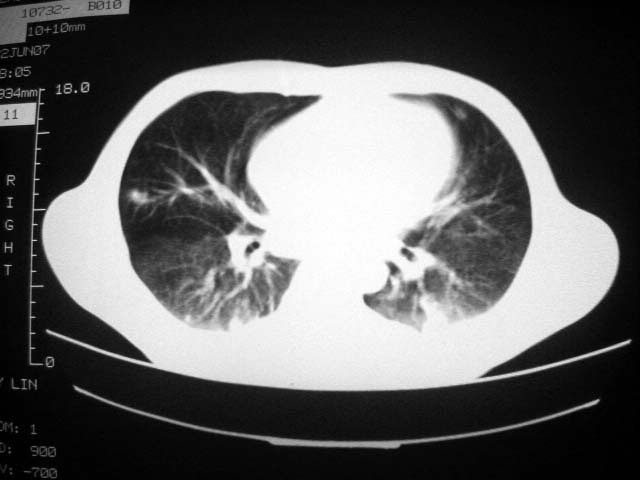

标题: CT7988D:近期图像 出乎意料!

从ct7988c 至今未用任何抗生素及抗痨药,维持保肝治疗。患者低热、咳血渐消失。

07年6月22号复查

前几次大家认为是转移癌,但此次复查病灶却明显吸收好转,不支持诊断。请大家讨论。[emb10]

bu不可思议,前三次都怀疑转移,但从这次的片子看仍有结节,就是比原来小